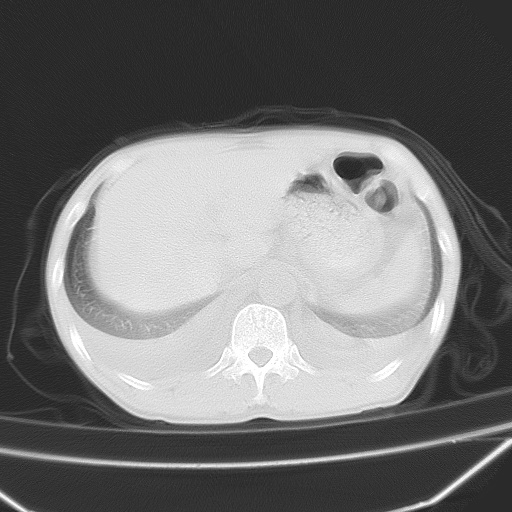

男、42岁、咯血3天。既往有甲亢、贫血、血尿蛋白尿史多年。血象:wbc:6.   中性粒:70.6%。

谢谢各位指导。刚才急查肾功能结果:肌酐1000多。尿毒症。

双肺野对称性磨玻璃影,分布于内中带,双侧胸水,患者有咯血。

1、间质性肺水肿;2、结合临床病史及实验室检查,考虑为肺出血肾炎综合征。    此病需与间质性炎症、粟粒性肺结核鉴别。

肺出血-肾炎综合征又称good-pasture综合征,属少见病,近几年国内有散在报告。此病原因未明,目前多数学者认为与自身免疫有关,即病人体内存在抗-gbm抗体,而病人肺毛细血管基底膜与肾小球基底膜有交叉反应性抗原,从而引起肺泡毛细血管基底膜和肾小球基底膜病变,导致肺出血及肾炎表现。血清抗-gbm抗体阳性,或组织活检见沿肾小球和肺泡基底膜有igg沉积,为本病的3个诊断依据。临床上有许多疾病同时表现为肺出血和肾炎,如系统性红斑狼疮、韦格肉芽肿和增殖性肾小球肾炎等,但这些疾病都不同时具备上述三方面的条件

双肺野广泛对称性磨玻璃影、实变影,以肺门为中心,主要分布于内中带,符合典型肺泡性肺水肿;伴双侧胸腔少量游离积液。结合患者既往病史且咯血就诊,支持多因素(尿毒症等)所致之肺水肿、肺出血、胸水;影像表现暂不考虑心源性水肿,且症状也不太符。需密切随诊结合临床治疗等进一步明确。